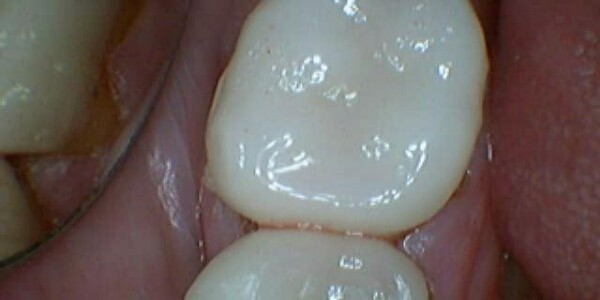

Restorative Dentistry

Restorative dentistry services focus on repairing teeth damaged to cavities, tooth decay, or trauma. From our beginning, it has been our goal to help our patients restore strength and structure to their smiles. We are committed to helping your smile stay beautiful and healthy for a lifetime. We incorporate the latest dental technology to ensure you receive the most advanced care. Our restorative services include:

Composite Fillings